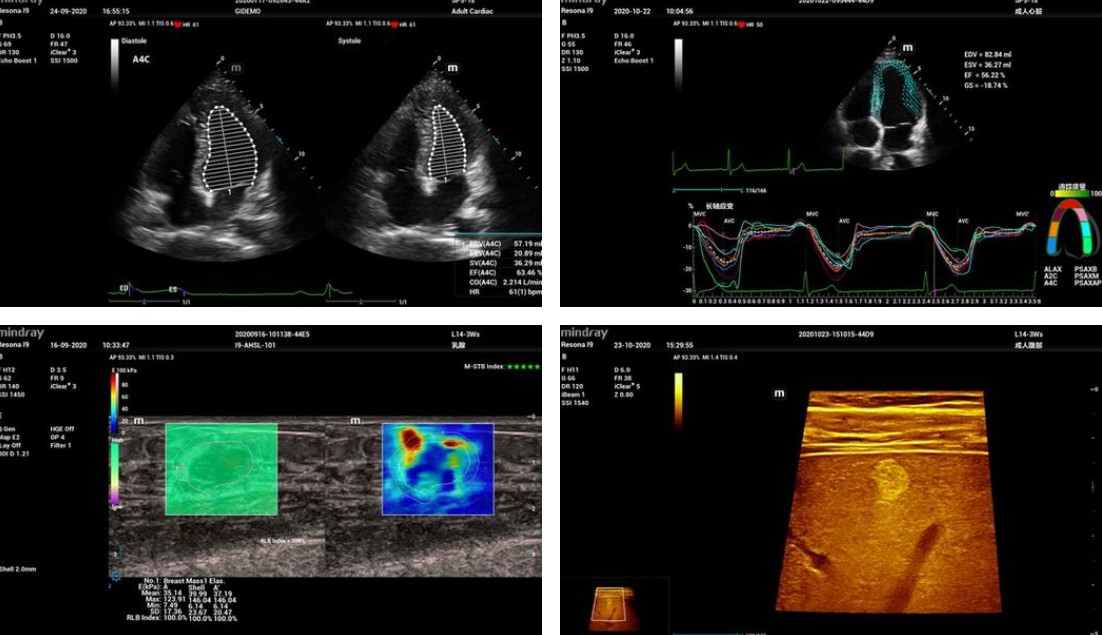

#Mindray's Resona I9 is a high-end ultrasound system designed to deliver an unrivalled diagnostic experience. Featuring the innovative ZST+ platform, it combines exceptional image quality, state-of-the-art ergonomics and remarkable clinical intelligence. With its accurate analysis tools, intelligent features such as Smart Breast and Smart Thyroid, and its foldable, quiet design, it adapts to all clinical environments. It offers unprecedented flexibility and increased productivity, ensuring reliable diagnosis and optimal patient care.

This system features an extensive suite of artificial intelligence (AI)-enhanced technologies, which improve reproducibility, optimize productivity, and increase consistency for end-users. The enriched Glazing Flow technology provides optimal visualization of micro-vascular perfusion states, while the Contrast-Enhanced Ultrasound (CEUS) imaging improves contrast and temporal resolution during CEUS studies. The Sound Speed Compensation (SSC) algorithm automatically detects and analyzes different tissue characteristics to determine the optimal signal speed needed for improved image quality. The system's Shear Wave Elastography (SWE) allows for smoother transition times and faster refresh rates, ensuring more consistent acquisition and assessment during live 2D shear wave imaging.